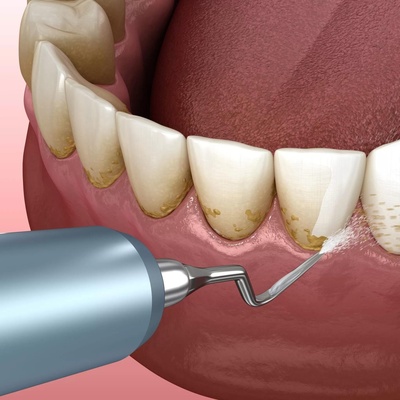

روش های خانگی جرم گیری دندان می تواند جایگزین مراجعه به دندانپزشک باشد؟

جوش شیرین برای جرم گیری دندان چه کاربردی دارد؟

سرکه و کاربرد های آن در جرم گیری دندان

چند روش خانگی برای از بین بردن جرم دندان

مسواک زدن صحیح دندانها چه تاثیری بر جرم دندان دارد؟

لزوم انجام جرم گیری دندان + نکات مهم

برداشتن پلاک با بروساژ دندان شامل چه مراحلی است؟

بهبودی و مراقبتهای بعد از عمل بروساژ

روشهای مختلف بروساژ دندان

چطور جرم دندان ها را کم کنیم؟

اصلا چرا باید جرم گیری کنیم؟